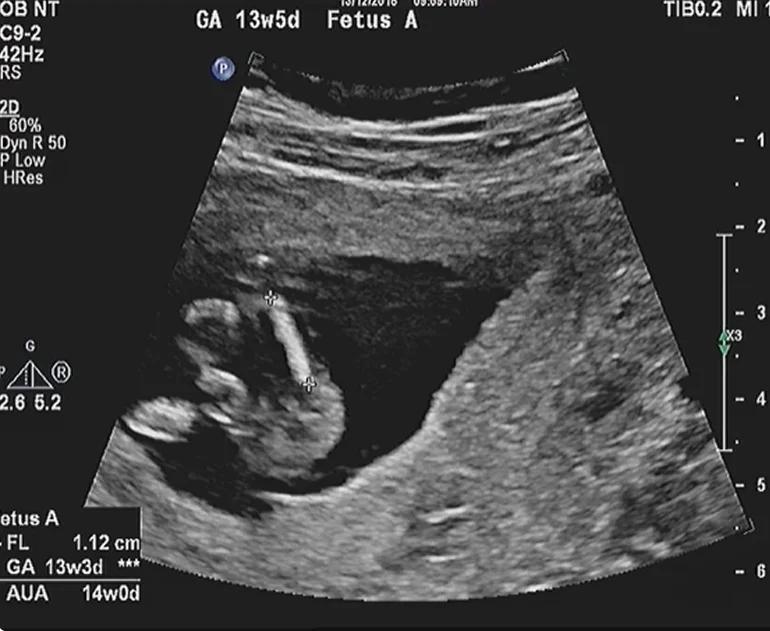

Dán nhãn và đánh giá tương hợp Song thai (Fetal Labeling & Concordance Assessment)